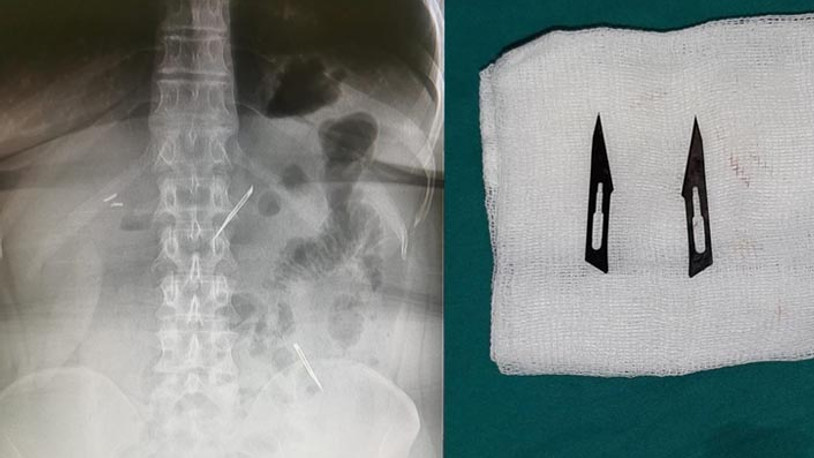

Başkent’te karın ağrısı şikayetiyle hastaneye başvuran 46 yaşındaki kadının midesinde 2 adet neşter tespit edildi. Neşterlerin vücuduna nasıl girdiğini bilmediğini söyleyen kadın, ekmek ile birlikte yutmuş olabileceğini ifade etti. Gerçekleştirilen başarı operasyon ile neşterler vücudundan çıkarılan kadının sağlık durumunun iyi olduğu öğrenildi.

Sağlık Bilimleri Üniversitesi Ankara Atatürk Sanatoryum Eğitim ve Araştırma Hastanesi'ne mide ve karın bölgesinde aşırı ağrı şikayeti ile müracaat eden 46 yaşındaki D.E.'nin yapılan tahlil, tetkik ve çeşitli görüntülemelerden sonra bağırsak kısmında 2 adet neşter olduğu tespit edildi. Genel cerrahi kliniği tarafından zorlu bir ameliyat sonrasında neşterler kadının vücudundan çıkarıldı.

46 yaşındaki D.E. neşterleri nasıl yuttuğunu bilmediğini tahminen ekmek ile birlikte yutabilmiş olabileceğini ifade etti. Ameliyatı gerçekleştiren Sağlık Bilimleri Üniversitesi Ankara Atatürk Sanatoryum Eğitim ve Araştırma Hastanesi Genel Cerrahi Kliniği Eğitim ve İdari sorumlusu Prof. Dr. Hakan Buluş ise hastanın yoğun şikayetleri üzerine çektikleri röntgen sonrasında 2 adet neşteri görünce şaşkına uğradıklarını söyledi.

Hastanın şikayetlerinin artması üzerine gerçekleştirilen tetkiklerde 46 yaşındaki kadının karın bölgesinde 2 adet yabancı cisim olduğunu tespit ettiklerini, detaylı inceleme sonucunda bu cisimlerin neşter olduğunu fark ettiklerini belirten Prof. Dr. Buluş, “Yaklaşık 10 gün önce kliniğimize karın ağrısı ve bulantı şikayetleri ile başvurdu. Bizim yaptığımız fiziki muayene ve tetkiklerinde hastanın direkt karın grafisinde 2 adet yabancı cisim olduğunu tespit ettik. Aslında yabancı cisim bizim güncel grafiğimizde sık karşılaştığımız bir durum değil, fakat nadir de olsa görebildiğimiz bir patoloji. Biz de bunun üzerine ayrıntılı değerlendirmeler ve tetkikler yaptık. Sonrasında 2 adet yabancı cismin bistüri (neşter) ile uyumlu olduğunu gördük. Bunun üzerine hastanın şikayetlerinin de artması üzerine, ameliyat kararı verdik. Yaptığımız ameliyatta ince bağırsağın yaklaşık 180'inci santimetresinde bu yabancı cisimlerin olduğunu tespit ettik. Bunun üzerine ameliyatla bunları çıkarttık. Hastamızın sağlık durumu şuan gayet iyi. Ameliyattan sonraki üçüncü günü. Şuan bir problemi yok, inşallah birkaç gün içerisinde şifa ile taburcu etmeyi düşünüyoruz” şeklinde konuştu.

Çıkardıkları cismin, neşterin normalde ameliyatlarda kullanılan bir malzeme olduğunu söyleyen Prof. Dr. Buluş, “Çıkardığımız yabancı cisimler bizim ameliyatlarda sıkça kullandığımız 11 numara dediğimiz bir bistüri tipi. Ebatları da yaklaşık 4 santime yarım santim ebatlarında. Ucunun sivri olması nedeniyle ince bağırsak mukozasına saplanarak enflamasyon ve bir karın ağrısı yapması, sonrasında da ağrı şikayetlerinin artmasına neden olmasından dolayı ameliyat kararı verdik” diye konuştu.